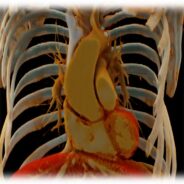

Pár kép az oktatás radiológiai részéről:

(SE-OKK, SIEMENS, CTISUS)